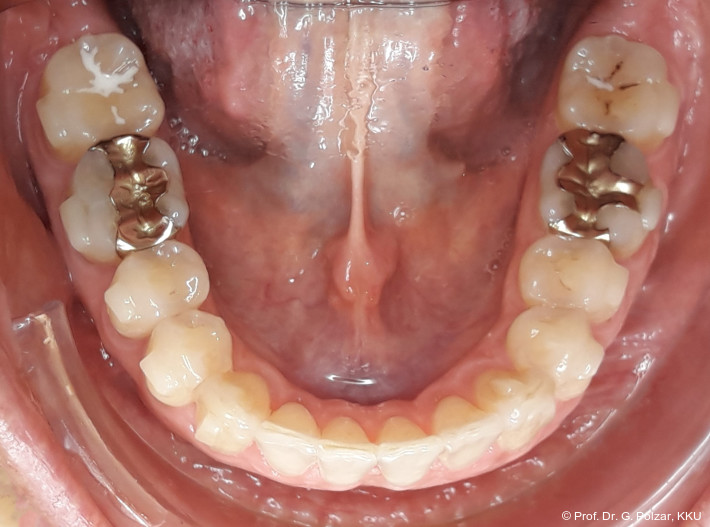

Der intraorale Befund zeigte eine scheinbar neutrale Verzahnung. Trotz Lingualretainer in der UK-Front war ein Engstand in der Unterkieferfront mit leichter Protrusion erkennbar. Appro­ximal des Zahnes 41 waren deutliche schwarze Dreiecke zu erkennen, zudem wies der Zahn eine leichte gingivale Rezession auf (Abb. 3a–f).

Nach weiteren acht Monaten Aligner-Therapie zur postoperativen Feineinstellung konnte die aktive Therapie weitgehend abgeschlossen werden. Mit einem CaseRefinement wurden die verbliebenen frontalen Lücken geschlossen (Abb. 17a–e).